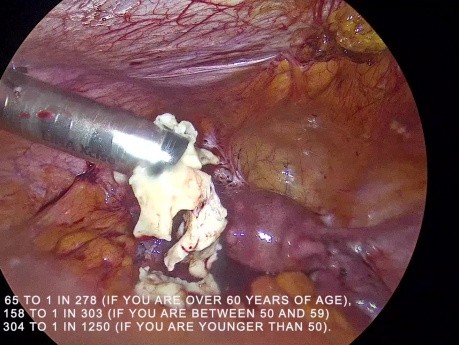

Morcelación contenida versus no contenida del...

La incidencia de diseminación del sarcoma cuando un fibroma se fragmenta con fuerza es muy variada. Puede variar de 1 en 65 procedimientos en una mujer mayor de 60 años a 1 en 1200 en una mujer que está...